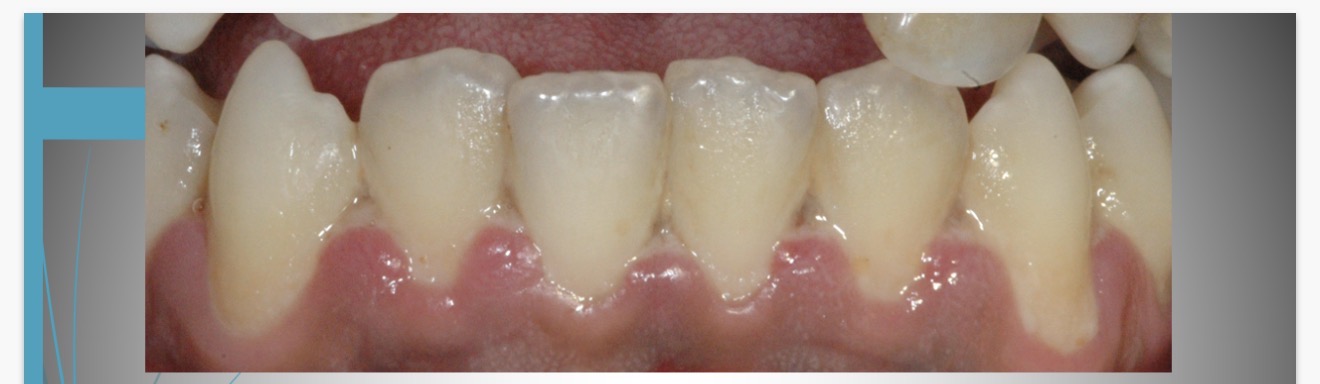

Condition?

Drug induced gingival enlargement

What drugs can cause gingival enlargement?

cyclosporine (SandimmuneĀ®)

dilitiazem (CardizemĀ®)

nifedipine (Procardia)

diphenylhydantoin (DilantinĀ®)